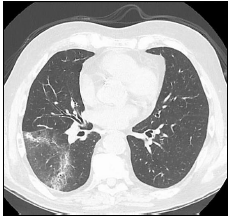

Observe a imagem de uma tomografia torácica:

A imagem possui um sinal que é altamente sugestivo de:

Pneumonia.

Bronquiectasia.

Edema agudo alveolar.

Tromboembolismo pulmonar.